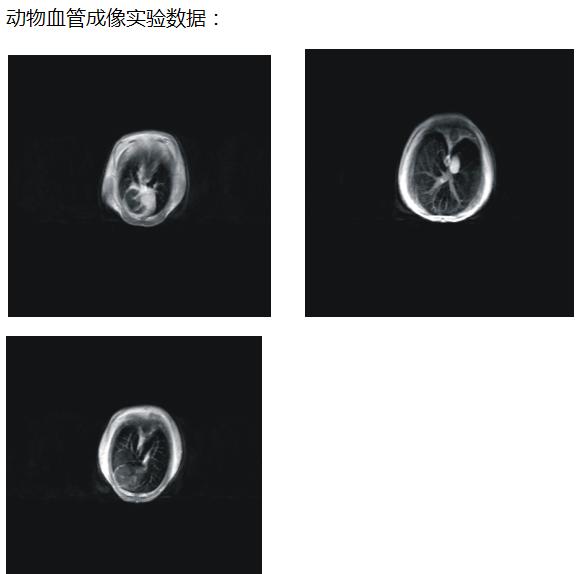

肿瘤鼠图片